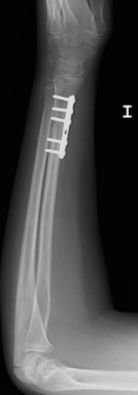

Figura 11: a, b-Fractura metafiso-diafisaria distal inestable. c, d-Control radiológico tras reducción donde se aprecia mala reducción. e, f-Síntesis mediante placa y tornillos.